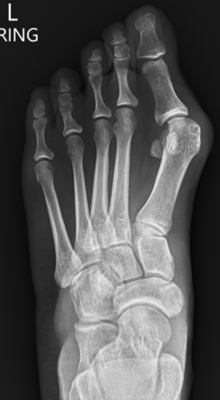

TOTAL ANKLE REPLACEMENT :: ORIF CALCANEUS :: ORIF ANKLE FRACTURE DISLOCATION :: COMPLEX BUNION AND LESSER TOE CORRECTION :: TALUS FRACTURE -1 :: TALUS FRACTURE -2 :: LISFRANC REPAIR :: COMPLEX TRIPLE ARTHRODESIS 1 :: COMPLEX TRIPLE ARTHRODESIS 2 :: MINIMALLY INVASIVE BUNION REPAIR 1 :: MINIMALLY INVASIVE BUNION REPAIR 2 :: ARTHROSCOPIC CARTILAGE REPAIR :: TENEX SPUR DEBRIDEMENT :: Haglunds Debridement and Achilles Repair